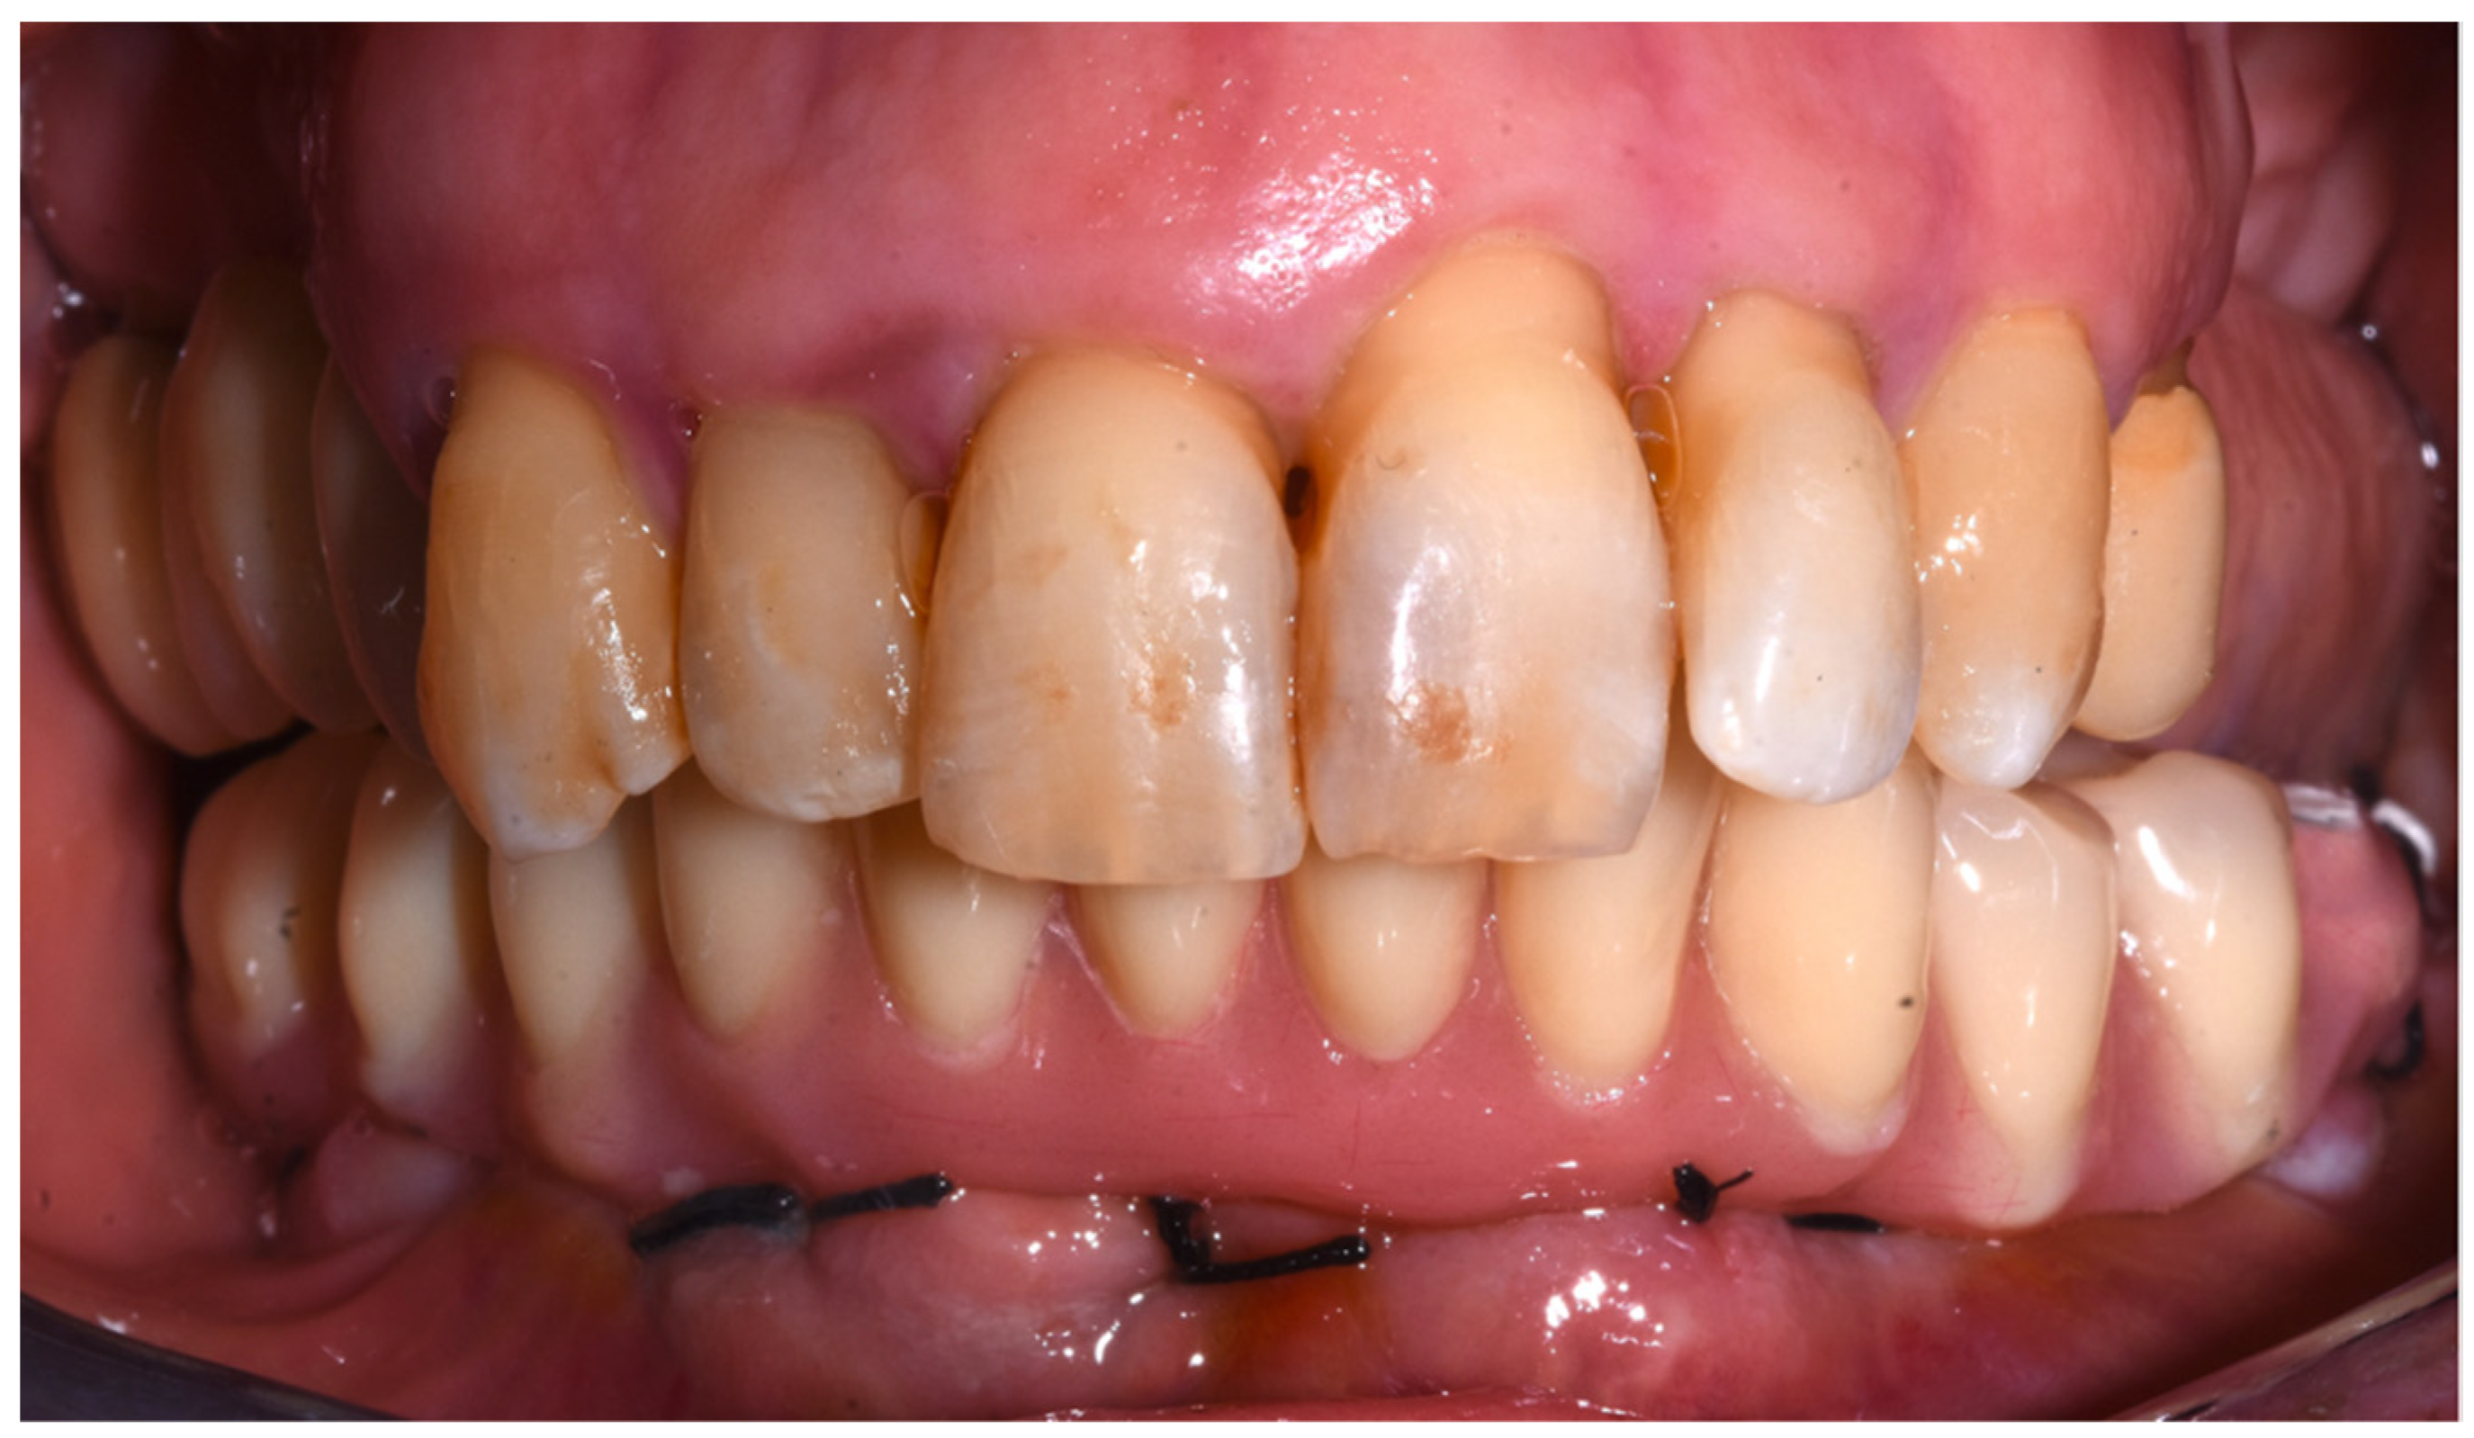

2. Case Report

3. Results